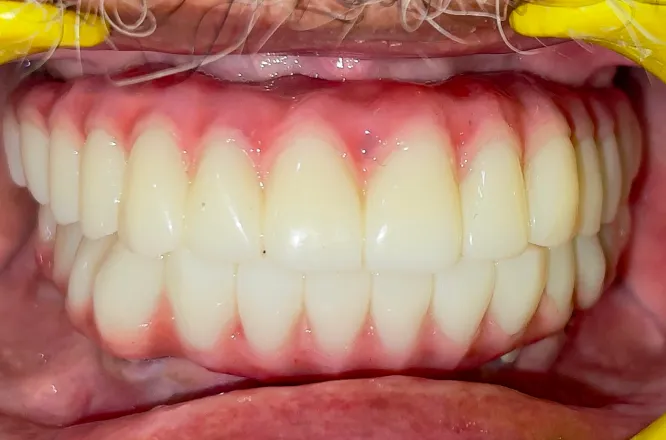

Form, function and aesthetics are at the forefront of our dental implant solutions. Single, multiple or full mouth dental implants are the best way to replace missing or damaged teeth with artificial fixtures that look, feel and function exactly like natural ones.

Implants work like natural teeth, letting you bite and chew your favorite foods without any discomfort.

Missing teeth can age your appearance. Implants restore your jawline, enhance your smile, and boost confidence.